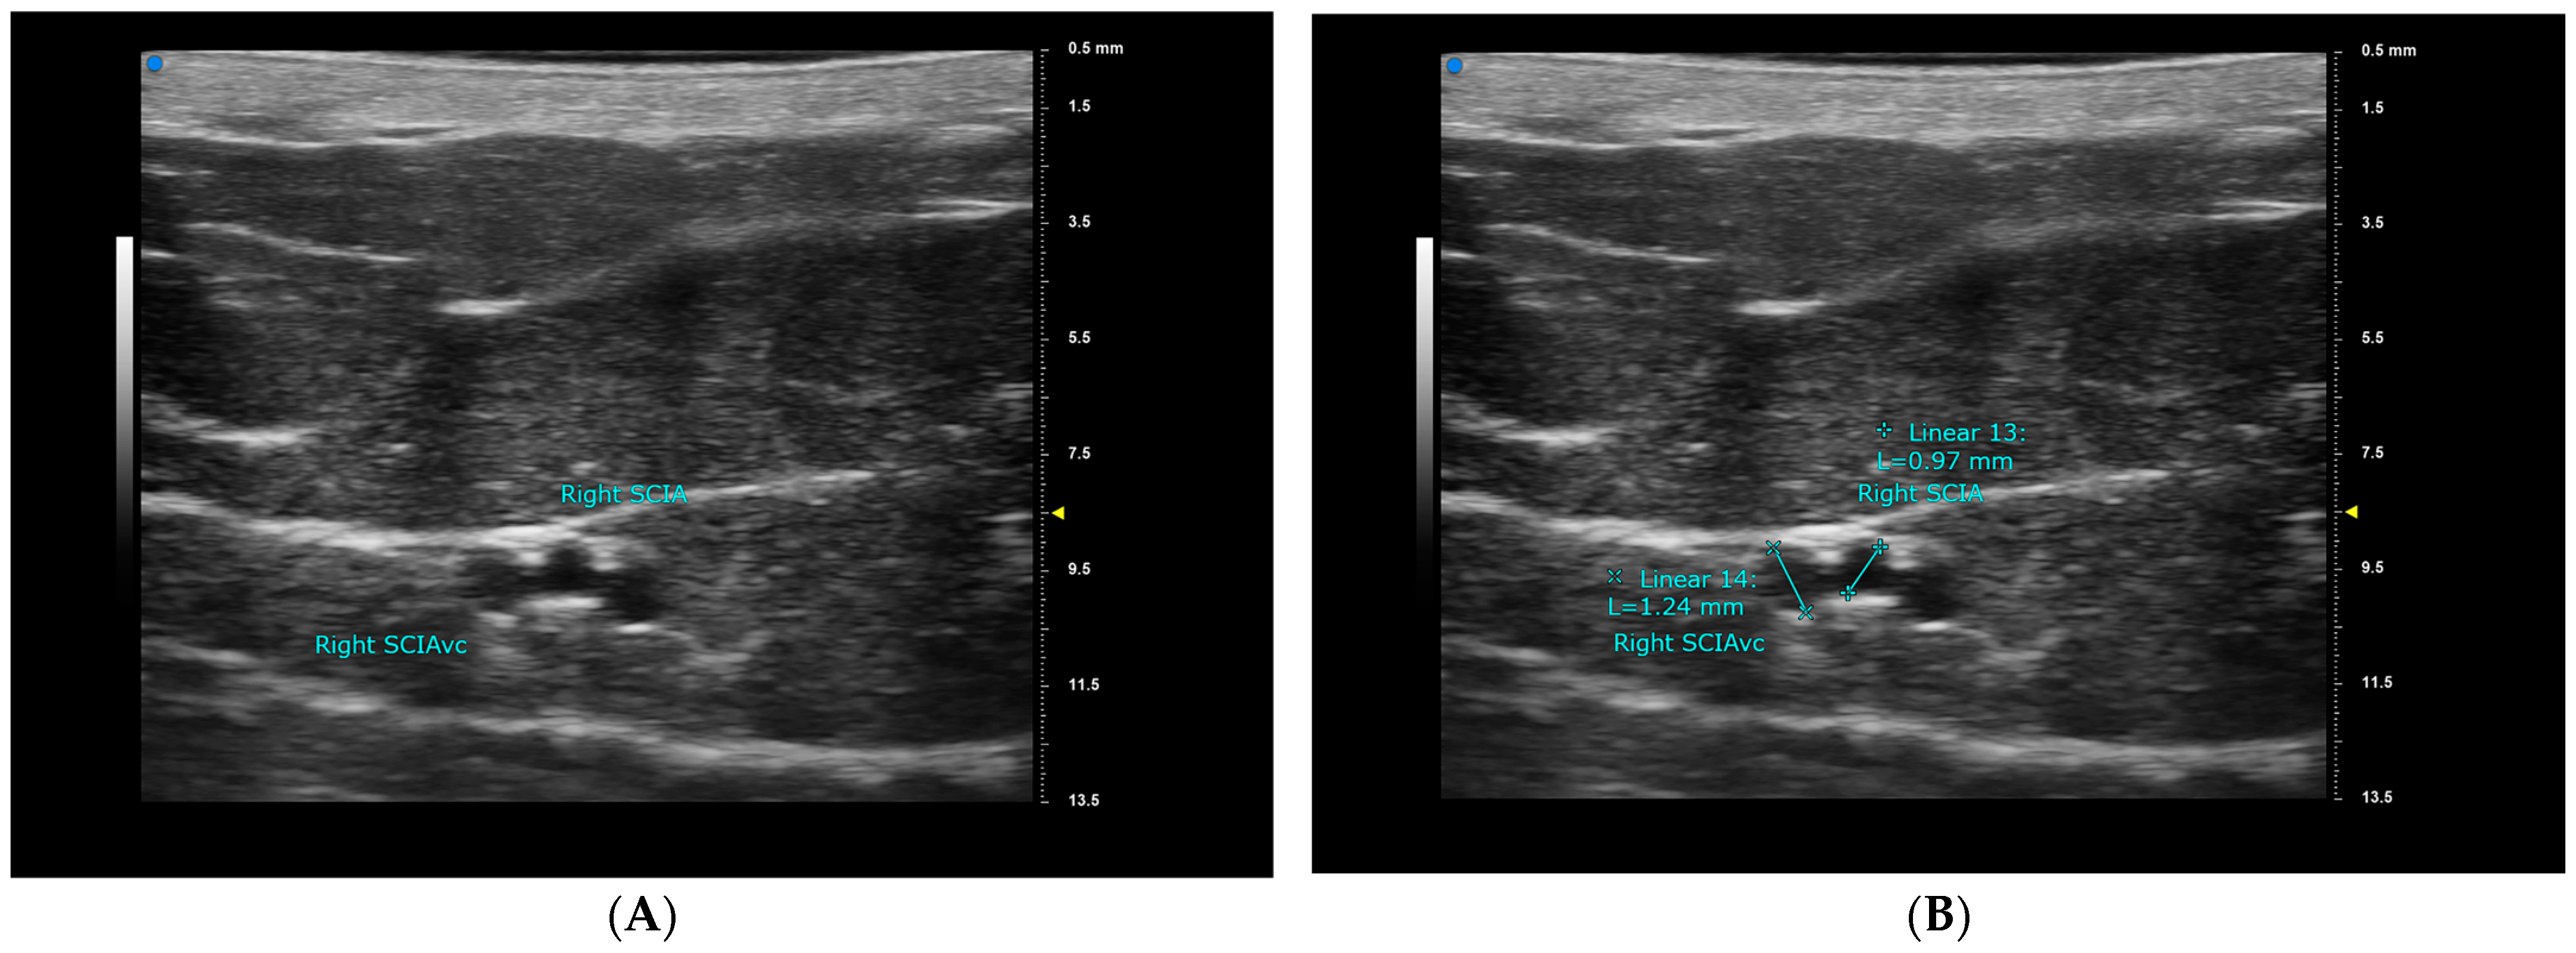

| SIEA | SIEA VC | SIEV | |

|---|---|---|---|

| detectable at ASIS level | 11/50, 22% | 8/50, 16% | 50/50, 100% |

| Average diameter at ASIS (mean ± SD, mm) | 0.63 ± 0.22 * | 0.64 ± 0.28 * | 2.18 ± 0.48 |

| Average depth at ASIS (mean ± SD, mm) | 4.94 ± 3.60 * | 4.94 ± 3.60 * | 3.46 ± 2.80 * |

| Average diameter when traced proximal (mean ± SD, mm) | 1.05 ± 0.20 * | 1.35 ± 1.06 * | 2.39 ± 0.57 |

| Average distance to midline (mean ± SD, mm) | 50.92 ± 22.26 * | 47.94 ± 10.11 (37.83−58.05 ǂ) | |

| Average distance to ASIS (mean ± SD, mm) | 51.32 ± 20.57 * | 62.63 ± 12.44 | |

| Superior-lateral pedicle course | 2/11, 18% | 2/50, 4% | |

| Superior pedicle course | 3/11, 27% | 10/50, 20% | |

| Superior-medial pedicle course | 6/11, 55% | 38/50, 76% | |

| Average SIEA-SIEV distance | 13.65 ± 14.88 * |